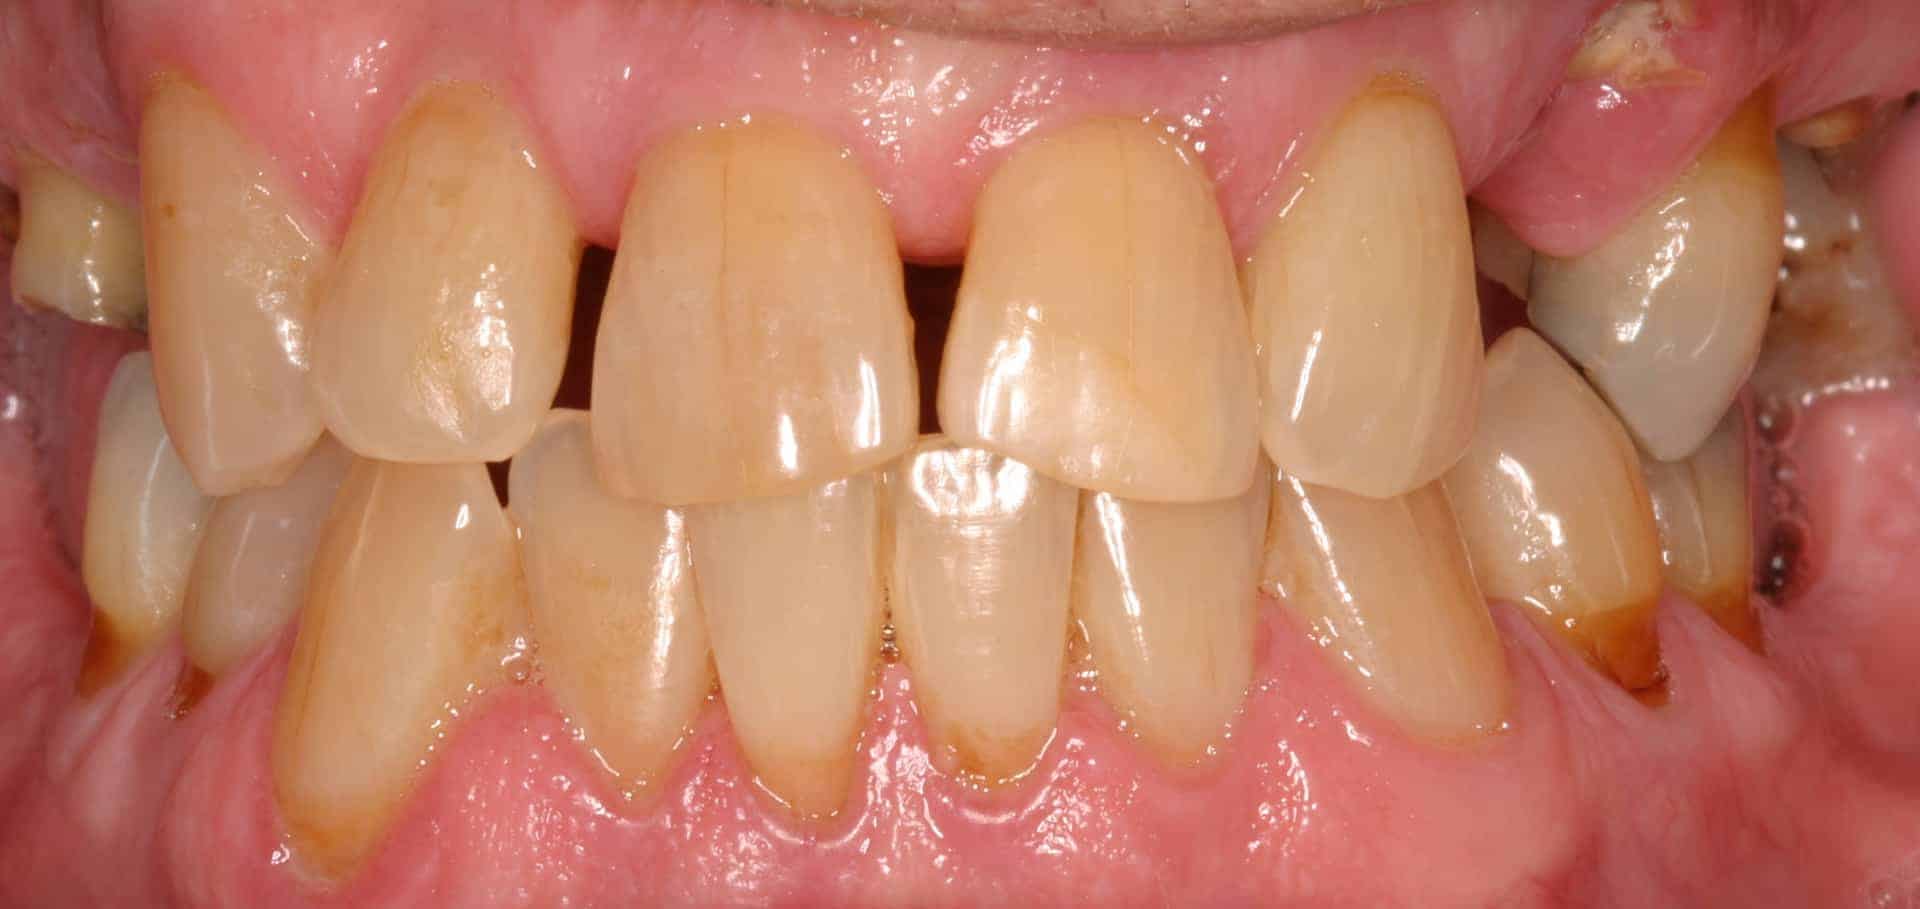

After: Maxillary (upper), acrylic fused to metal, fixed (hybrid) screw-retained (retrievable) restoration supported by 6 titanium root form dental implants. The restoration is fixed, therefore only Dr. Leopardi can remove it for routine maintenance and hygiene, as needed. The patient cleans the fixed restoration as he does his natural lower teeth, with a tooth-brush, floss and water-pick. The outcome is improved function, mastication/diet, aesthetics and quality of life.